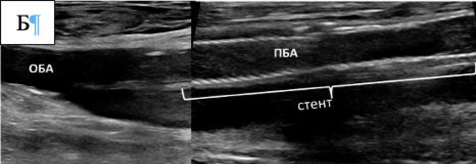

После чрескожной пункции общей бедренной артерии (ОБА) достаточно часто возникают паховые гематомы. Для предотвращения данного осложнения следует избегать сквозной пункции общей бедренной артерии.

• Рекомендуется проводить пункцию под ультразвуковым контролем с целью точного прокола передней стенки артерии и минимизации риска повреждения задней стенки [185, 186].

Комментарий: Анализ пяти РКИ показал, что пункция артерии под УЗ-контролем снижает частоту осложнений по сравнению с пункцией по анатомическим ориентирам [180]. Использование УЗИ уменьшало число попыток пункции (ОШ 0,24), риск прокола вены (ОШ 0,18) и кровотечений (ОШ 0,41). Сравнительных данных об эффективности антеградного и ретроградного доступа при тромболизисе нет. Антеградный доступ через ОБА упрощает реканализацию тромбозов дистальных артерий, а через артерии верхней конечности – прохождение через тромбированную бифуркацию аорты. Ретроградный контралатеральный доступ через ОБА наиболее распространён, обеспечивает стабильное положение катетера и снижает риск смещения и кровотечения [181]. Этот доступ также позволяет избежать необходимости сдавления ОБА ишемизированной нижней конечности при гемостазе, после удаления набора для чрескожного сосудистого доступа (интродьюсер) из места пункции.

• При выполнении эндоваскулярного вмешательства пациентам с острой ишемией конечностей рекомендуется проводить пункцию артерии доступа под ультразвуковым контролем [181].